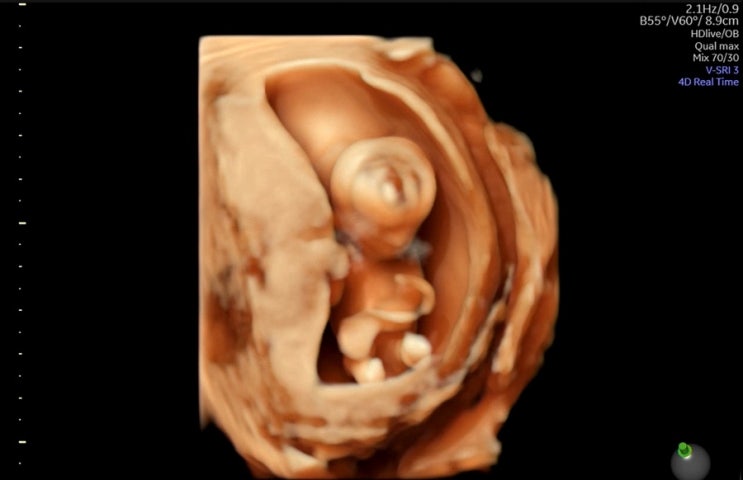

임신일기 12주차 : 태아보험 심사 거절?, 1차 기형아 검사, 정밀초음파, 니프티 할말?

임신일기6 안녕하세요 미니뷰입니다:) 벌써 12주차가 되었어요! 시간이 진짜 빠르기도 하고, 몸의 변화도 ...